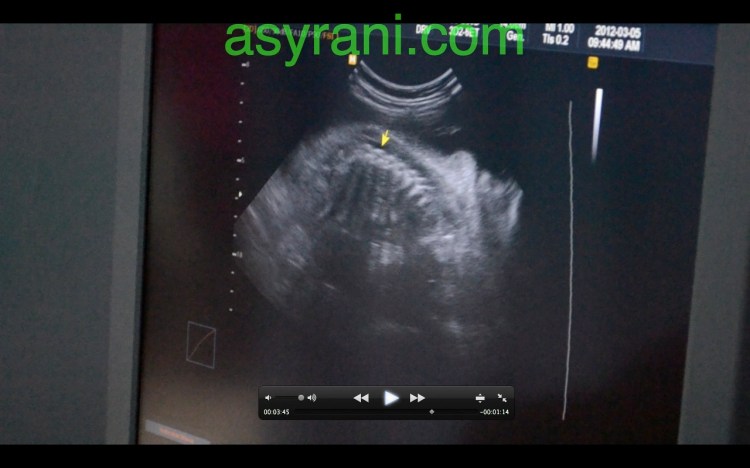

Kawasan gelap itu menandakan air kentuban mengcukupi.

Anak panah menunjukkan Four Chamber jantung baby